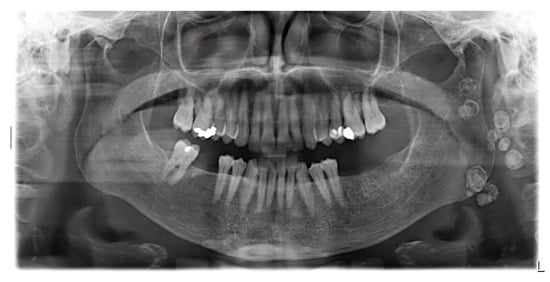

Enigmatic Formations Found in Routine Orthopantomography (OPG) Examinations: A Case Report

2. Case Presentation